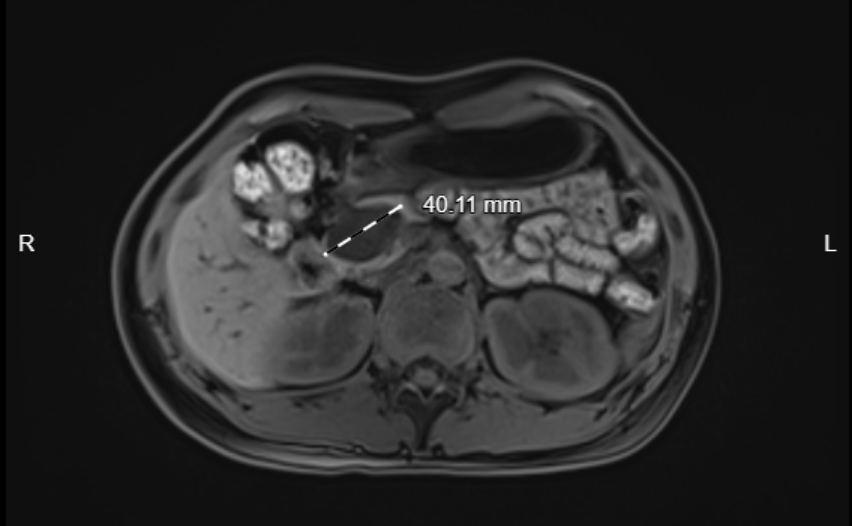

早在3年前体检时,经上腹部增强磁共振,陈女士发现了自己的胰腺有一块40*28mm的占位,初步考虑胰头部囊性病变,囊腺瘤,同时肝脏也有较小的血管瘤和囊肿。

陈女士的小心谨慎并没有换来囊肿的持续稳定。根据医嘱,陈女士每年都会定期复查自己胰腺囊肿的情况,前两年的影像报告提示她的胰腺囊肿并没有变大。可到了今年,陈女士再次体检时却发现胰腺上的囊肿在短短一年里迅速增大至68*42mm,这令她一下子慌了神。

通过磁共振胰胆管成像(MRCP)的影像片子来看,陈女士的胰腺囊肿已经非常贴近主胰管,普通的手术方式无法规避在剜除囊肿时伤害到主胰管的风险,若是主胰管受到了机械性伤害导致破裂,胰液由非生理途径外流,则会发生非常严重的并发症——胰瘘,严重时可引起毒血症、败血症、多器官功能衰竭等情况,后果不堪设想。